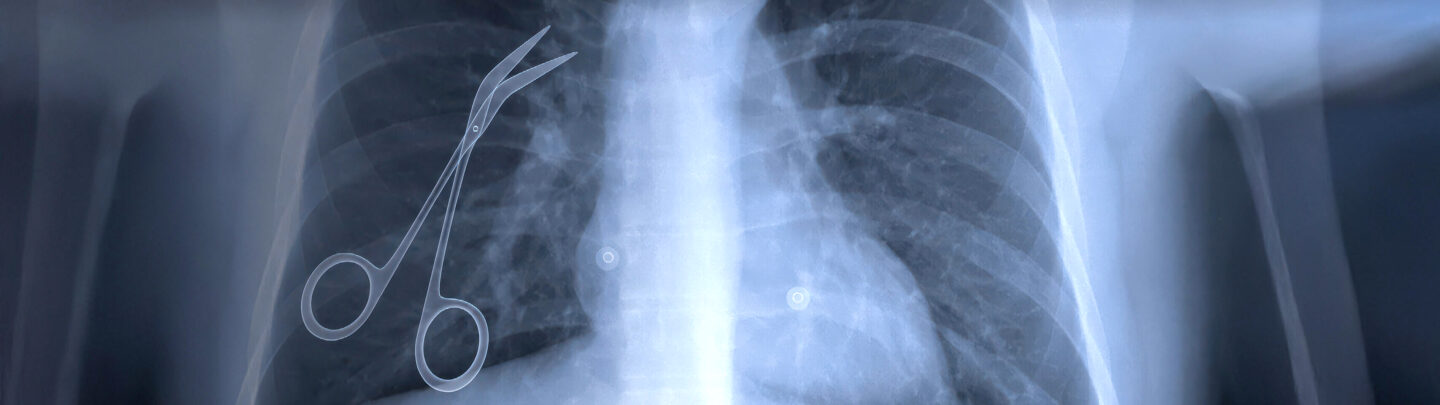

X-ray image of a human chest showing a pair of surgical scissors left inside the upper left side of the chest cavity.

Medical malpractice occurs when a doctor, nurse, or medical facility fails to provide care that meets the recognized standard, resulting in harm, injury, or even death. This can include misdiagnosis, surgical errors, medication mistakes, or negligent treatment. Under California law, victims must prove that a medical professional’s actions deviated from the accepted standard of care, causing direct harm. If you have been harmed by medical malpractice or negligence, Baker, Burton & Lundy’s experienced attorneys will fight for justice and the compensation you deserve.

Some of the many types of medical malpractice cases we handle are birth injury, defective medical devices, medication mistakes and dangerous drugs, nursing home and elder abuse, surgical mistakes and anesthesia errors.